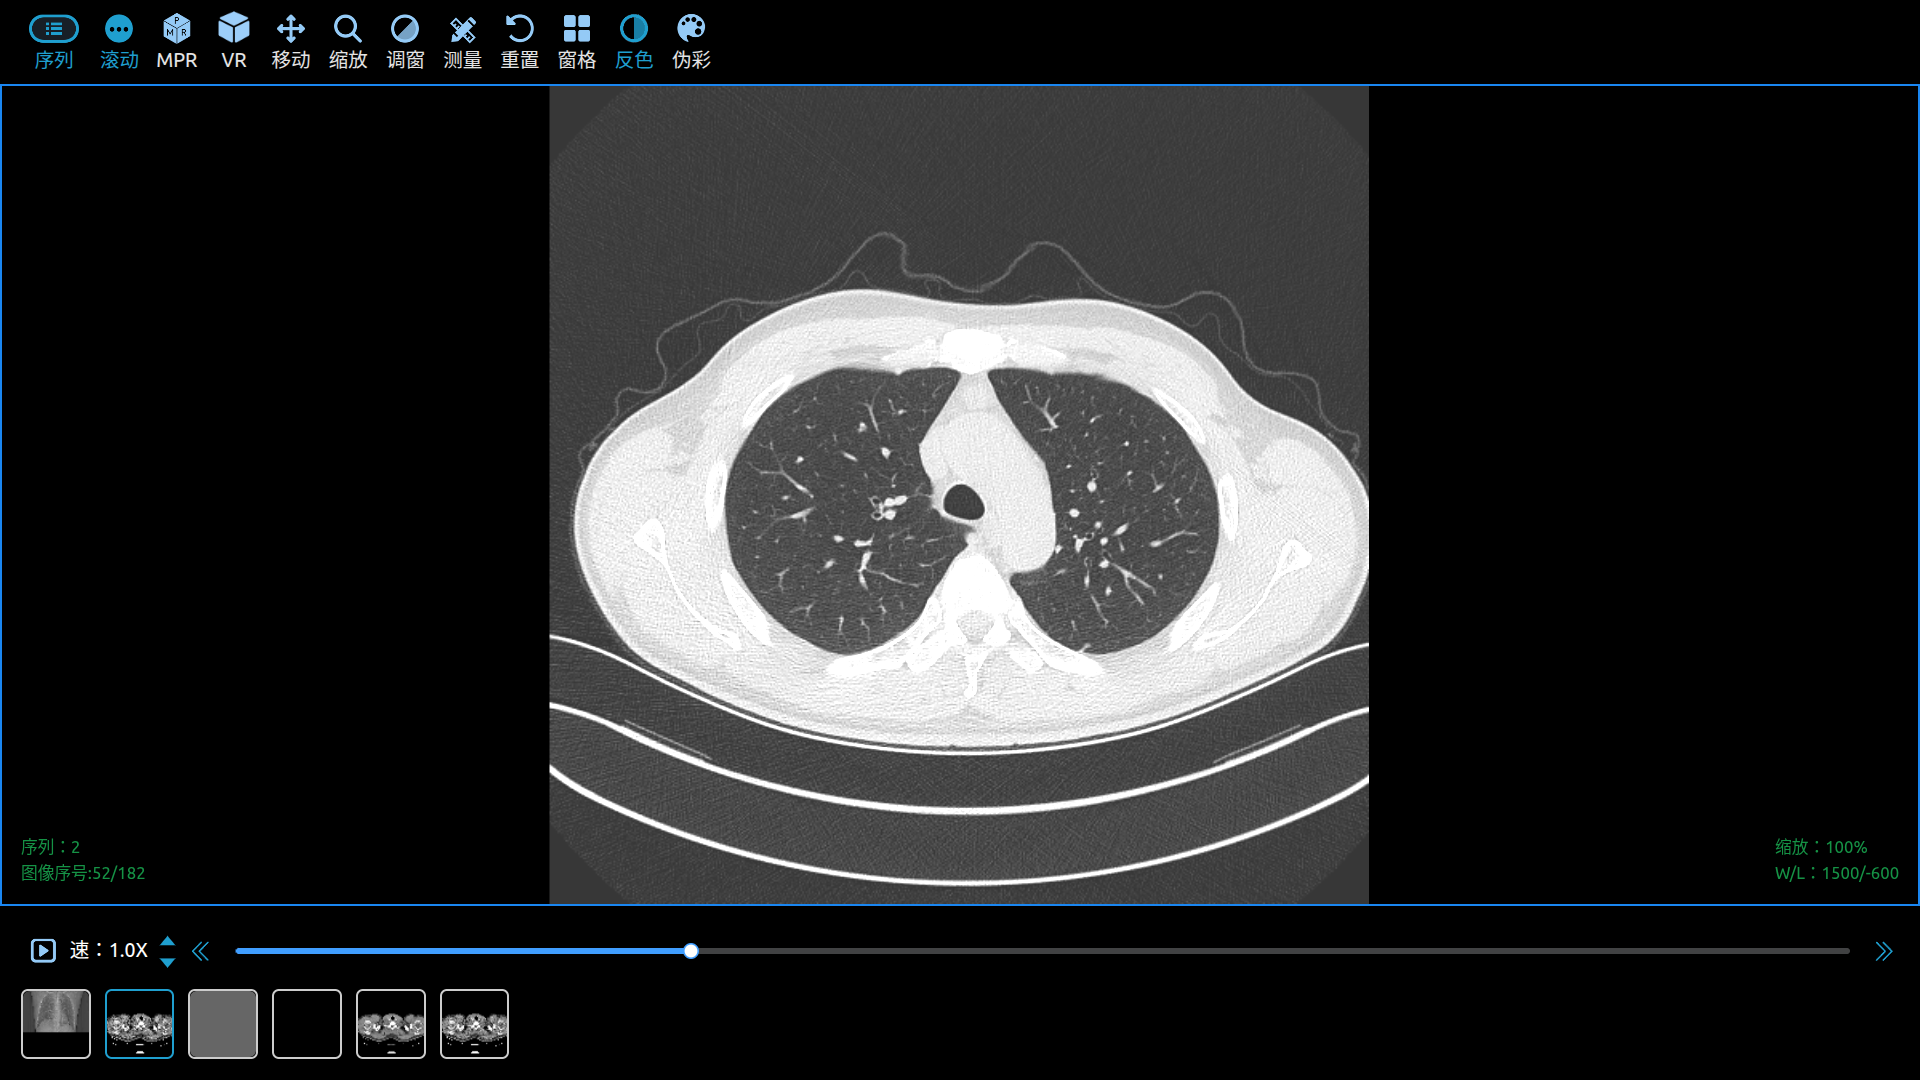

Use Cornerstone3D to View DICOM Images in a Web Browser.